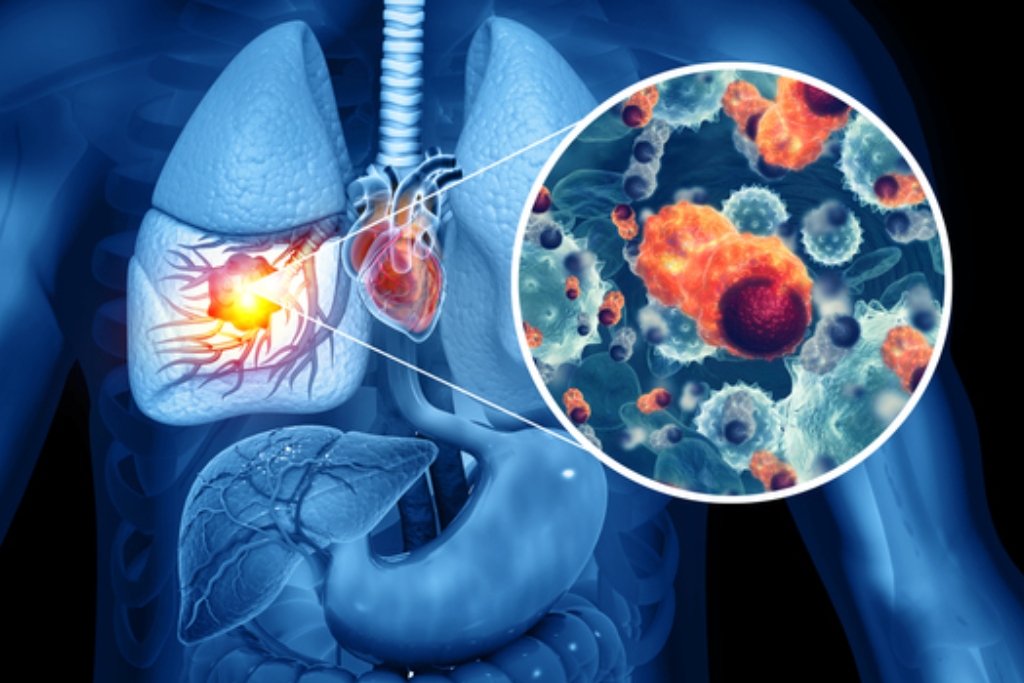

Lung Cancer

Lung cancer is a serious disease caused by abnormal growth of lung cells, often requiring early diagnosis and specialized pulmonary care.